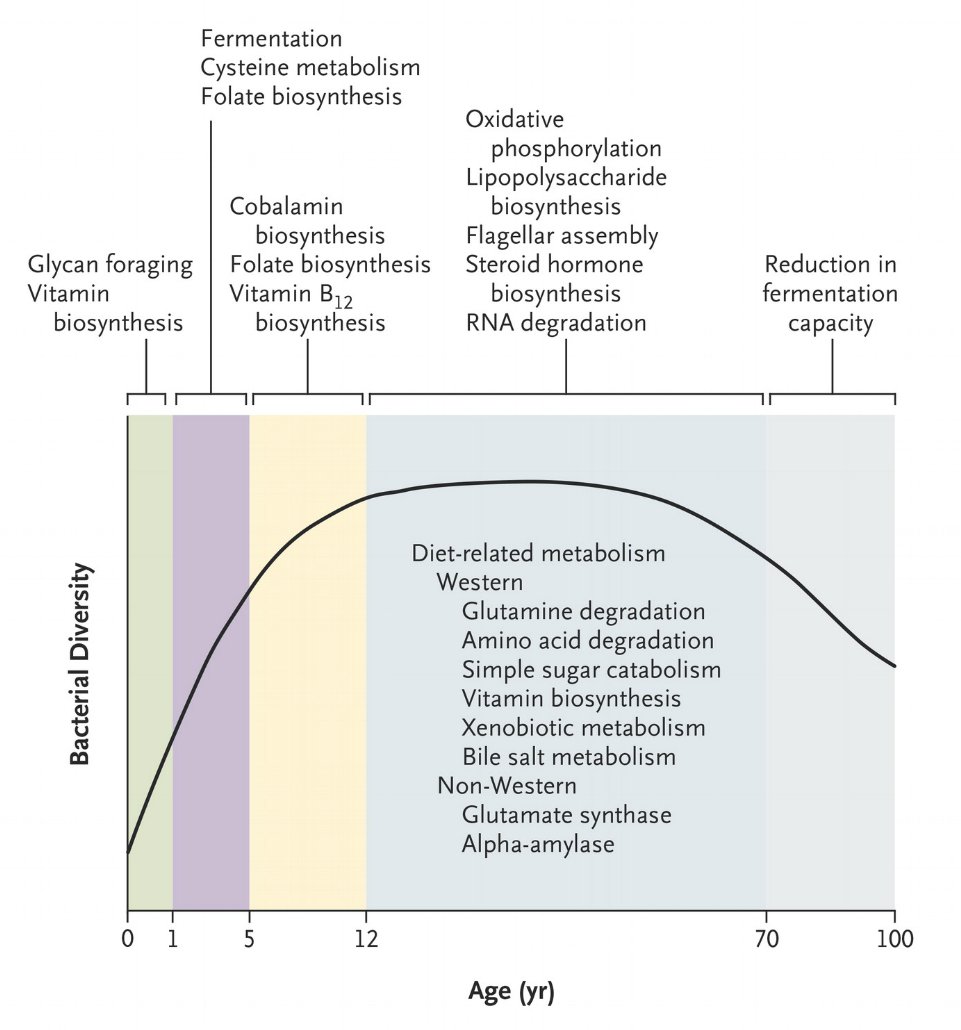

Temporal Development of the Gut Microbiota in Humans. Read the full Review Article: http://nej.md/2hESXOw pic.twitter.com/TQSqriPu0a